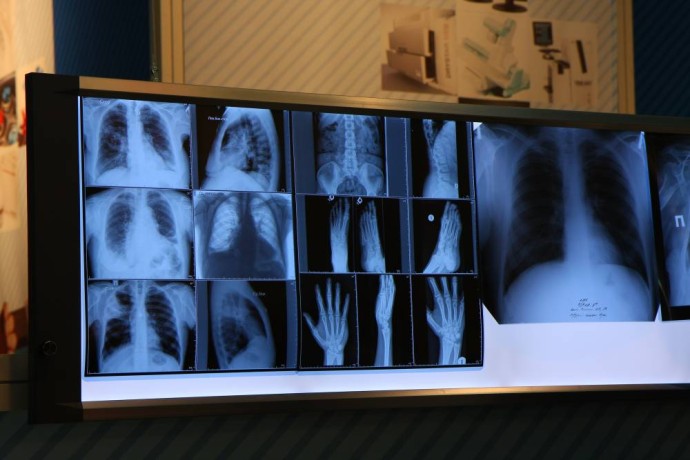

Ленинский районный суд Перми вынес приговор по делу о мошенничестве и сбыте фальсифицированных рентгеновских аппаратов в медицинские учреждения края. Руководители двух коммерческих организация отправлены в исправительную колонию общего режима на срок от 6 до 6,5 года. Также каждому назначен штраф в 500 тыс. рублей и запрещено в течение трех лет заниматься производством, изготовлением, реализацией медицинских изделий.Как сообщили в СУ СКР по Пермскому краю, в 2020 году между компаниями виновных и региональными властями были заключены контракты на поставку медизделий. По ним организации направили в лечебные учреждения региона рентген-аппараты, не отвечавшие условиям контракта и требованиям безопасности пациентов. Оборудование было изъято, а его эксплуатация запрещена. Причиненный ущерб бюджету Пермского края составил 120 млн рублей.